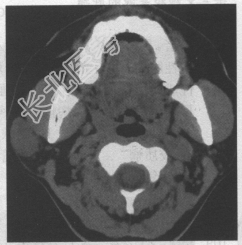

- 单项选择题患者,女, 30岁。无意中发现右侧面部包块半年余。CT检查如下图,诊断为

A、腮腺混合瘤

B、腮腺淋巴瘤

C、腮腺神经鞘瘤

D、腮腺畸胎瘤

E、腮腺囊肿